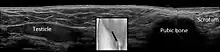

| Cryptorchidism on scrotal ultrasound | |

In the minority of cases with bilaterally nonpalpable testes, further testing to locate the testes, assess their function, and exclude additional problems is often useful. Scrotal ultrasound or magnetic resonance imaging performed and interpreted by a radiologist can often locate the testes while confirming absence of a uterus. At ultrasound, the undescended testis usually appears small, less echogenic than the contralateral normal testis and usually located in the inguinal region. With color Doppler ultrasonography, the vascularity of the undescended testis is poor.